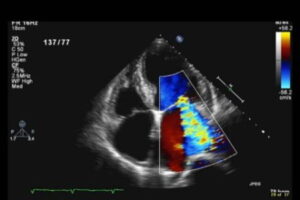

Ecocardiograma

Ecocardiograma e doppler de carótidas e vertebrais: exames fundamentais para avaliação cardiovascular completa

Ecocardiograma: O exame que revela a saúde do seu coração